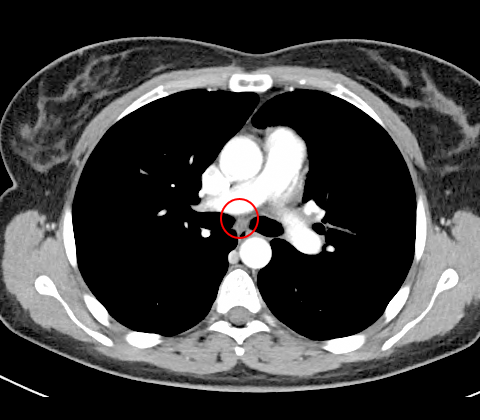

Tomografia computadorizada

A tomografia computadorizada mostra um tumor na divisão brônquica principal esquerda dos lobos superior e inferior (fig.1) e um pequeno linfonodo na estação linfonodal 7 (fig.2).